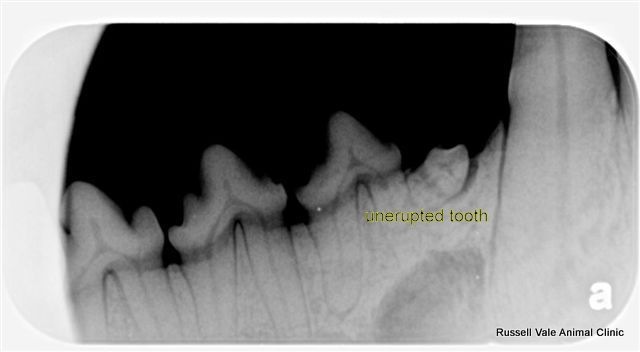

A common public perception of "veterinary upselling" is dentistry, but it doesn't deserve that tag at all. As a vet who does alot of dentistry on "normal looking mouths" only to find the dental disease underneath, I shudder to think of the pain the pet would've been in if I hadn't intervened. Candy (pictured below) is a classic case in point, but I have many many others too - as have many of my colleagues who perform quality veterinary dentistry (with dental radiographs).

Vets who promote good dental practices are not upselling, but are actually providing you and your pet an opportunity towards identifying painful disease, and removing it.